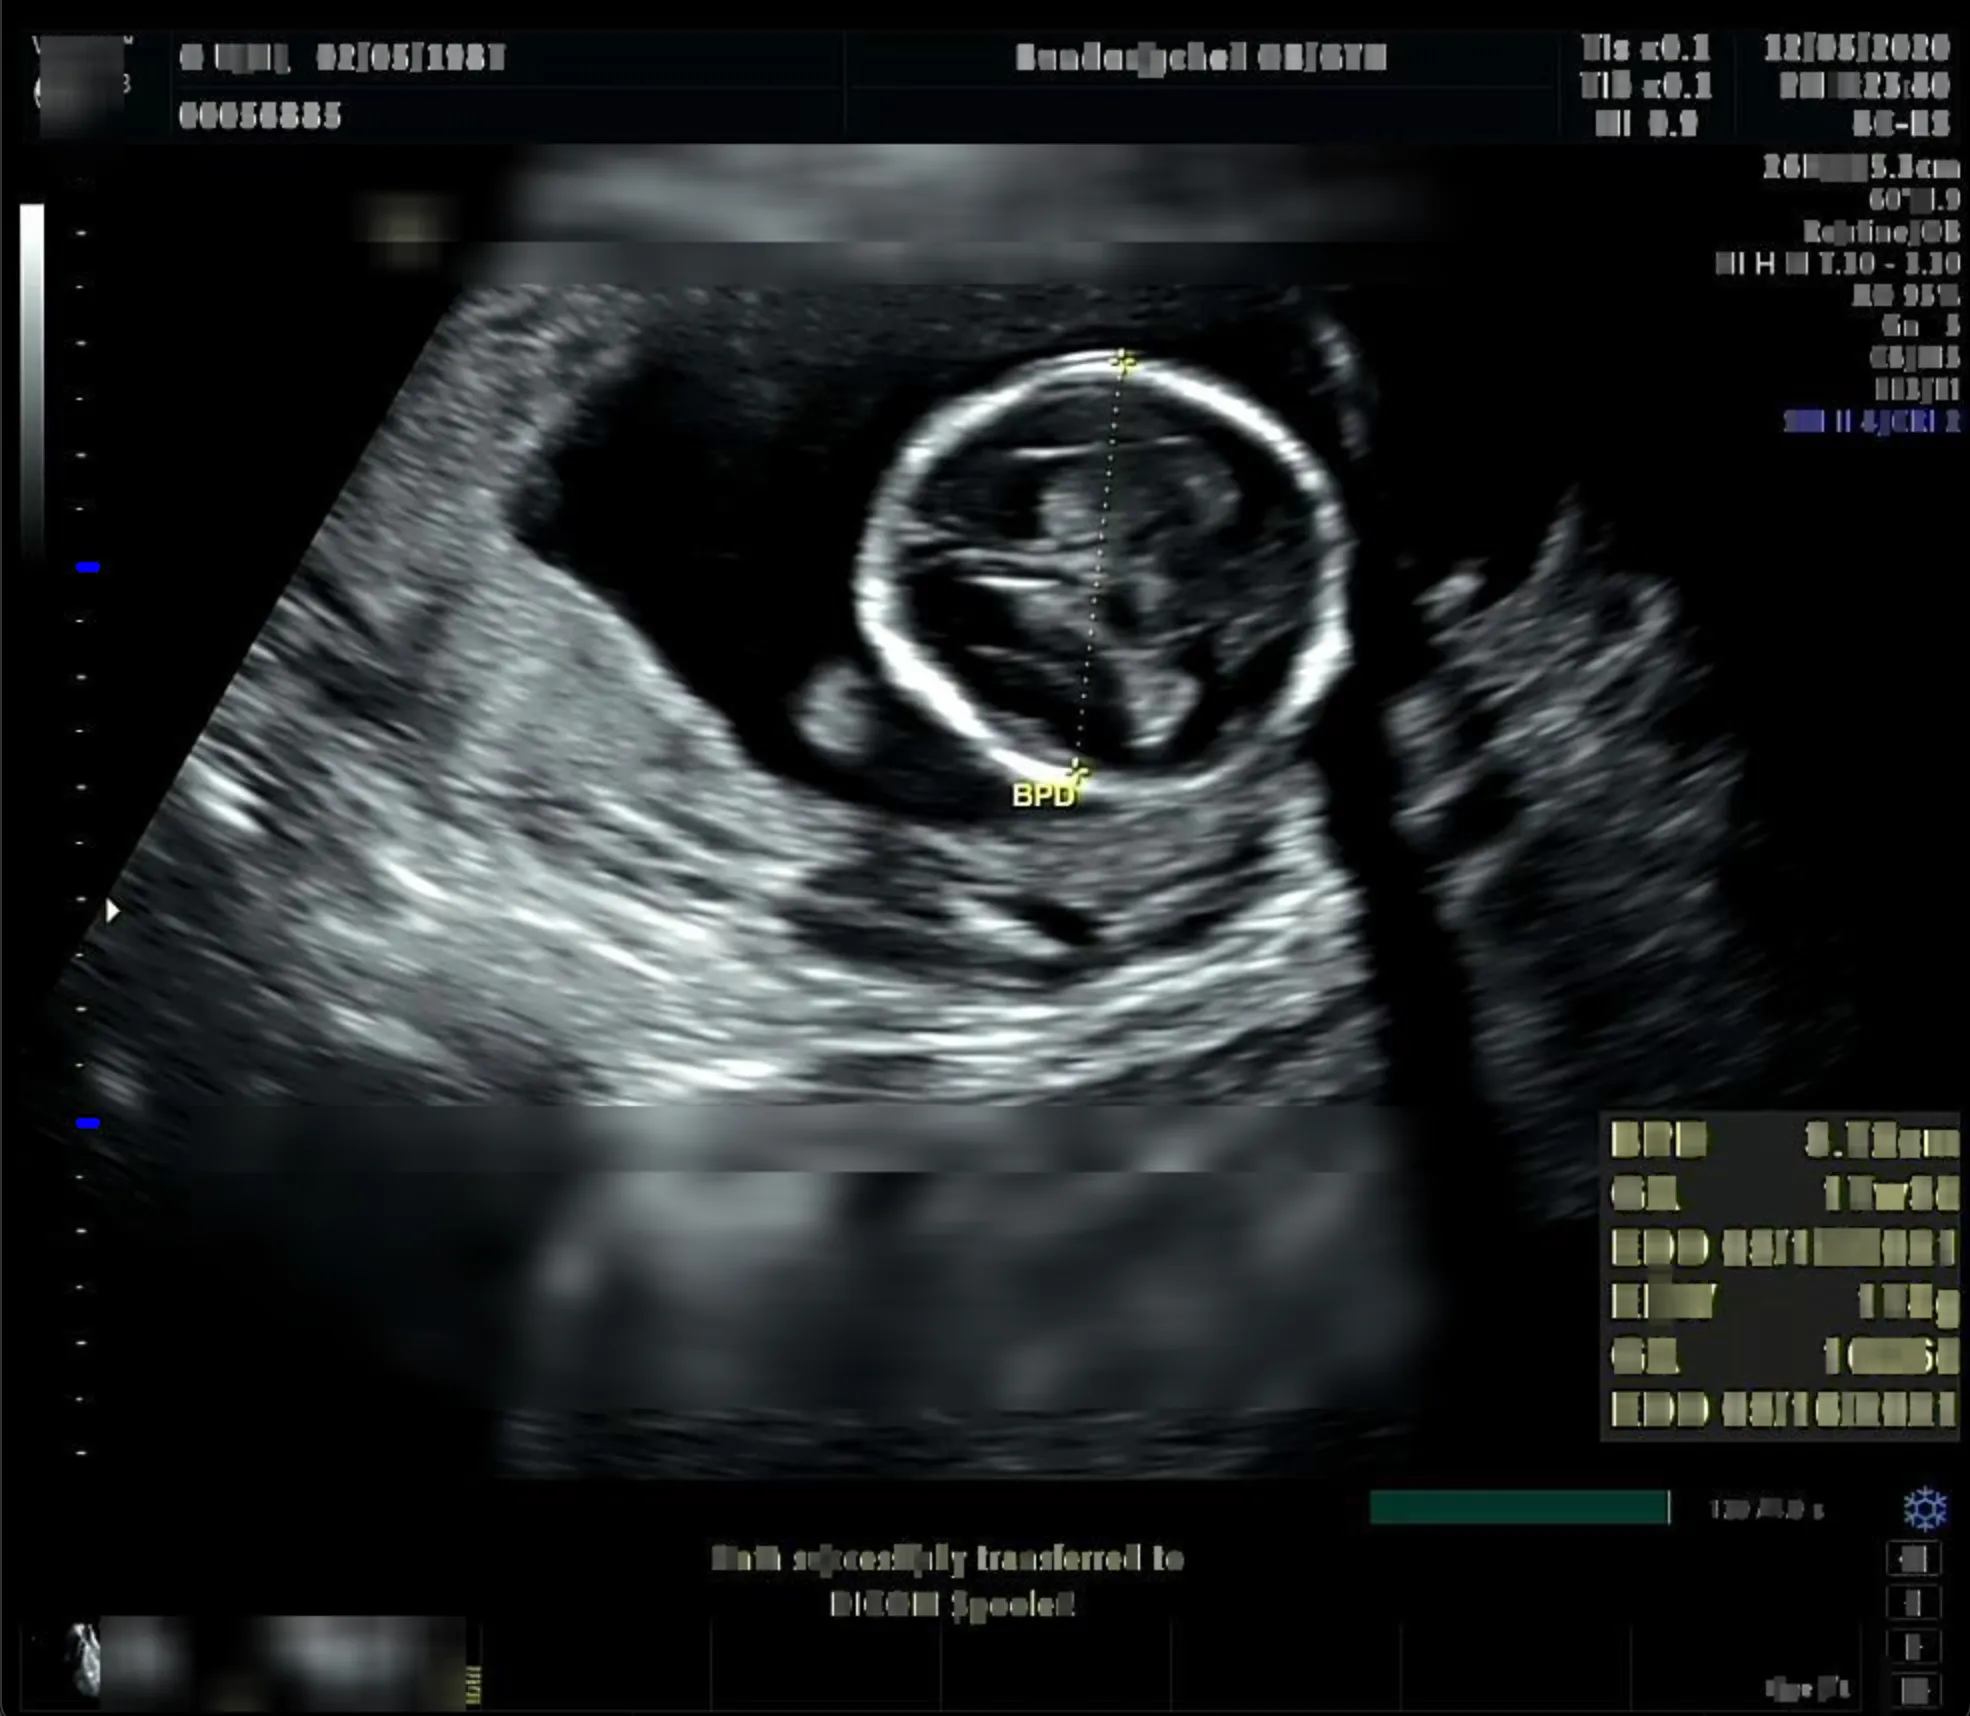

초음파 진단 장비마다 스케일바의 위치가 정말 다양했다. 좌측 혹은 우측이었다. 우선 스케일바 영역을 찾는 것부터 먼저 진행했다. 이어서 눈금 간격을 측정해서 픽셀 당 거리로 환산했다. 가장 굵은 눈금을 측정하는 것에 집중했다. (파란색으로 강조) 그 이유는 모든 눈금을 측정하려다 보니 온갖 점들이 인식되어 노이즈가 발생헀다. 그래서 파란색 눈금 사이의 픽셀 거리를 구하고 cm 당 픽셀 거리로 계산하여 배율을 구했다. 그런데 이 과정에서 사실 내가 간과한 치명적인 오류가 있었다. 😭 눈금 간격을 무조건 1cm 로 간주했다는 점이다.

첫 번째 사진은 실제로 눈금 간격이 1cm 였다. 하지만 두 번째 사진은 그렇지 않았다. 눈금 간격이 1cm 가 맞다면 왼쪽 눈금의 전체 길이는 최소한 20cm 가 넘는다. 그런데 실제로 측정된 BPD 는 3.72cm 였다. 여러 이미지를 테스트하면서 픽셀 거리를 어림짐작하여 배율을 구하는 if-else 문을 만들게 되었다. 당장 프로토타입으로는 문제가 없지만 장기적으로는 올바른 판단이 아니라고 생각했다. 방법을 찾고 싶었다. 초음파 이미지를 뚫어지게 쳐다보며..

방법을 찾았다. BPD 가 측정된 꽤나 많은 태아 초음파 이미지를 보면 스케일바 하단에 YYcm 인지 또는 XXHz/YYcm 라는 영역이 출력되고 있었다. 즉, 물리적인 거리를 표현하고 있었다. 그래서 이미지의 해상도 정보를 획득한 후 ”물리적인 거리 / 해상도의 높이” 연산을 통해 배율값을 얻었다.